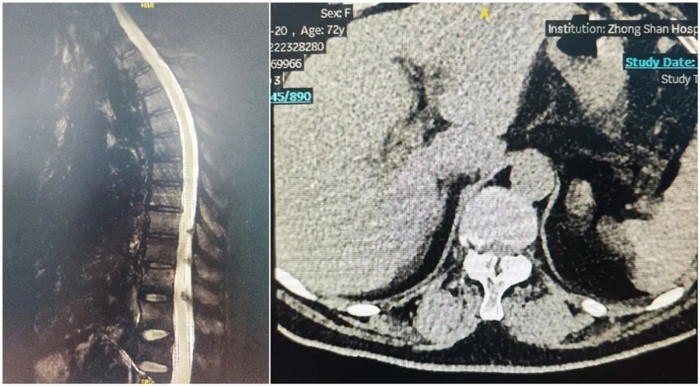

患者两年前出现左侧胸背部皮肤感觉麻木,有束带感,左上臂皮肤感觉麻木,否认肌力减退,胸平扫椎CT示:胸椎序列正常,生理弯曲存在,椎体边缘骨质增生,椎间盘略退变,T7-T9黄韧带增生并伴骨化,压迫内膜囊,椎管狭窄。影像诊断:黄韧带骨化。

术前影像